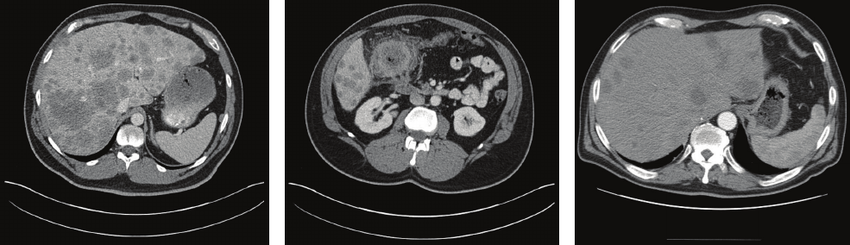

Deep-learning algorithms are excellent at pattern-matching in images; they can be trained to detect different types of cancer in a CT scan, differentiate diseases in MRIs, and identify abnormalities in an x-ray. But because of privacy concerns, researchers often don’t have enough training data. This is where GANs come in: they can synthesize more medical images that are indistinguishable from the real ones, effectively multiplying a data set to the necessary quantity.”